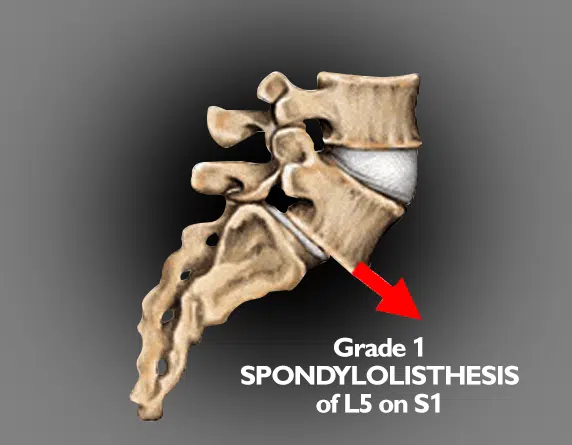

Spondylolisthesis is a condition where one vertebra slips forward over the one beneath it. This can occur in any part of the spine but is most commonly seen in the lower back (lumbar region). The slippage may create spinal instability and, in some cases, place pressure on nearby nerves.

Imaging is used to confirm the diagnosis and assess the severity of slippage:

- X-rays – The primary test for detecting vertebral slippage and measuring its degree. Standing X-rays may show instability when bending forward or backward.

The combination of clinical examination and imaging helps determine the type and severity of spondylolisthesis, guiding the most appropriate treatment plan.